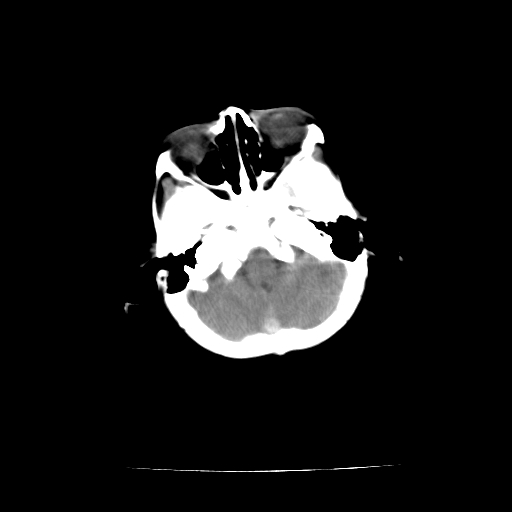

女,10个月,头外伤三天,伤后爱哭闹,吃奶少,睡觉不踏实。

左侧颞极蛛网膜囊肿

1)左侧颞极蛛网膜囊肿。2)第四脑室出血?

1、左侧颞极蛛网膜囊肿;2、第四脑室出血?3、右侧顶叶脑裂畸形伴灰质异位?

1)左侧颞极蛛网膜囊肿。2)第四脑室内高密度影,性质待定。